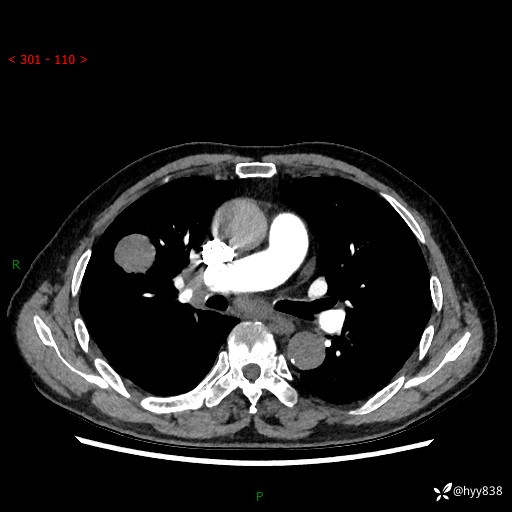

69岁/男,间断咳嗽伴气促、下肢水肿。临床拟诊肺栓,偶发肺均质强化结节--结果公布

【患者信息】:69岁/男

【主诉】:间断咳嗽伴气促、下肢水肿2周

【现病史及既往史】:患者2周来无明显诱因出现咳嗽,咳少量白痰,不易咳出,伴有气促,呈间断发作,症状与活动费力相关,以夜间为甚,不能平躺入睡,偶有憋醒,无胸闷胸痛、无发热、无头晕、头痛等不适,伴有双下肢中度水肿,就诊于当地县人民医院门诊,完善相关检查提示:左下肢深静脉血栓形成,未予以特殊处理,今患者为求进一步诊治来我院就诊,拟“心衰”收入我科。 起病以来,患者精神、饮食、睡眠可,大小便如常,体力明显下降,体重未见明显减轻。

【检查】:胸部CT增强